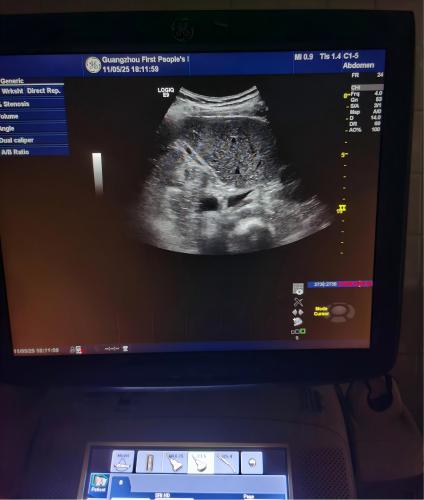

检测结果:GE LOGIQ E9彩超的MRX192板件损坏。

维修结果:更换MRX192板件后,图像采集正常,设备正常使用。

GE LOGIQ E9彩超4387-3.jpgGE LOGIQ E9彩超4387-4.jpg